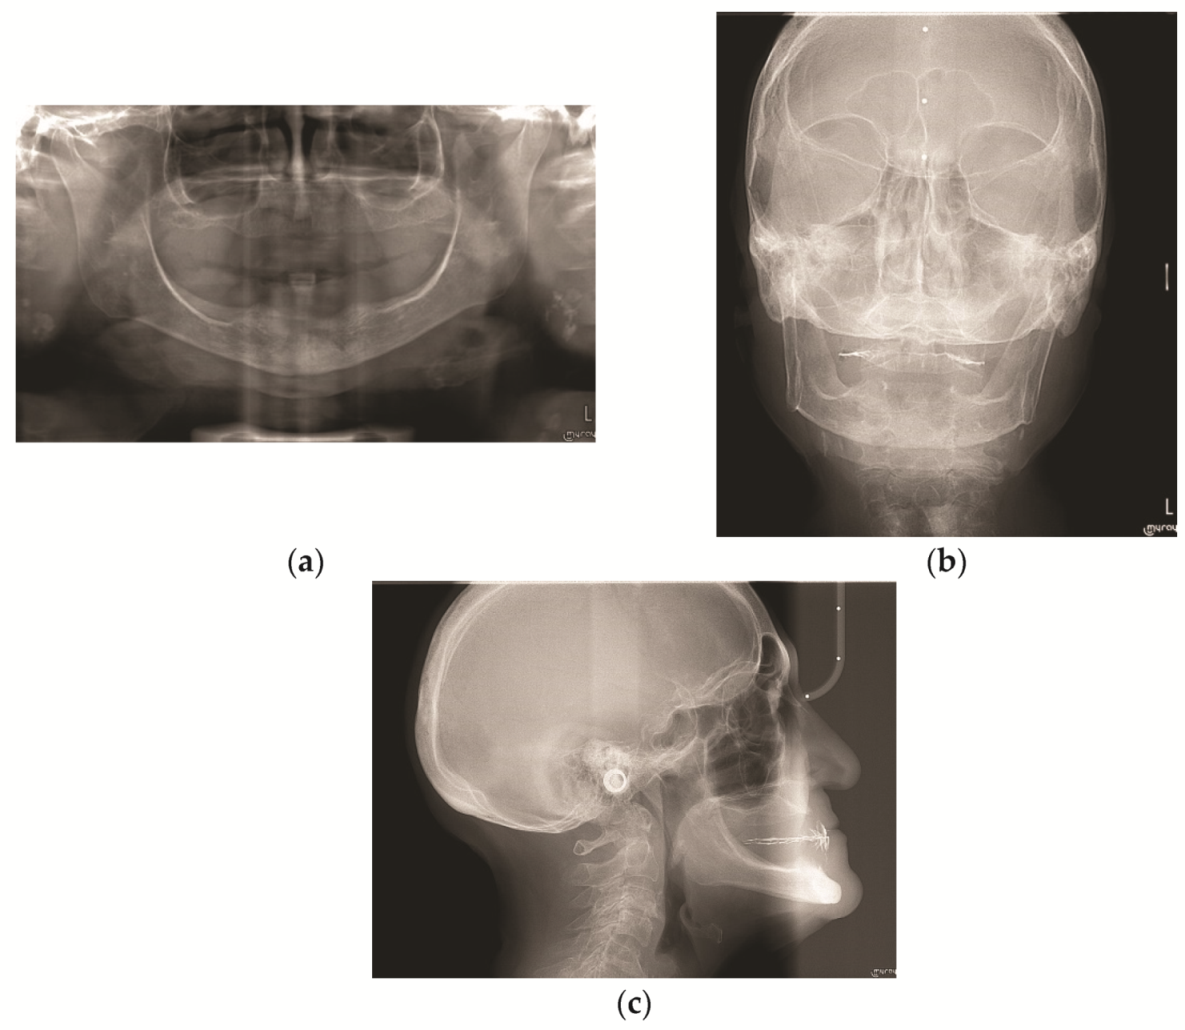

After the anamnestic data collection, a physical examination (intra-oral and extra-oral) was performed and it revealed a generalized muscle and joint pain upon palpation. Keeping the old complete removable prostheses in the oral cavity, occlusal contacts were analyzed, intra- and extra-oral photographs were taken, and routine radiographic examinations were carried out: orthopantomography (OPT) (Figure 2a), antero-posterior teleradiography (AP Ceph) (Figure 2b), and latero-lateral teleradiography (Lat Ceph) (Figure 2c).

Figure 2.

Initial radiographic images: (a) initial orthopantomography (OPT); (b) initial antero-posterior teleradiography (AP Ceph); (c) initial latero-lateral teleradiography (Lat Ceph).